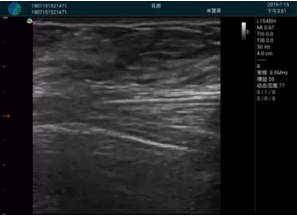

可視化穿刺引導(dǎo)

M20實(shí)時(shí)引導(dǎo):向包塊后方間隙注射利多卡因

清晰顯示腺體內(nèi)低回聲快影,邊界清晰,包膜較光滑

確定進(jìn)針路徑并實(shí)時(shí)監(jiān)測(cè)抽吸針與腫塊位置關(guān)系

抽吸針進(jìn)入腫塊內(nèi)部進(jìn)行旋切

抽吸過程中可見腫塊明顯縮小,并根據(jù)腫塊位置改變針道位置

抽吸旋切后再進(jìn)行超聲復(fù)查,原腫塊區(qū)域未見殘留組織及出血

超聲引導(dǎo)下抽吸旋切取出的腫塊組織